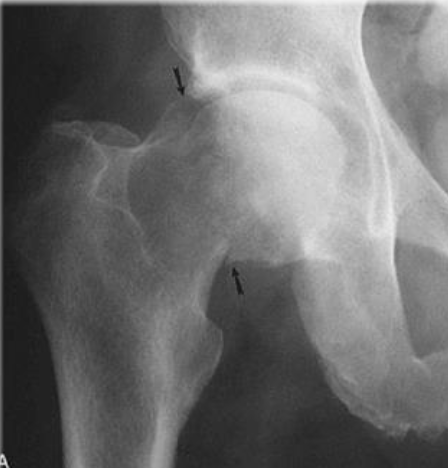

AP of Hip OA with Pseudocysts

(Top Down) Femur, Osteophyte, Sclerosis, Tibia